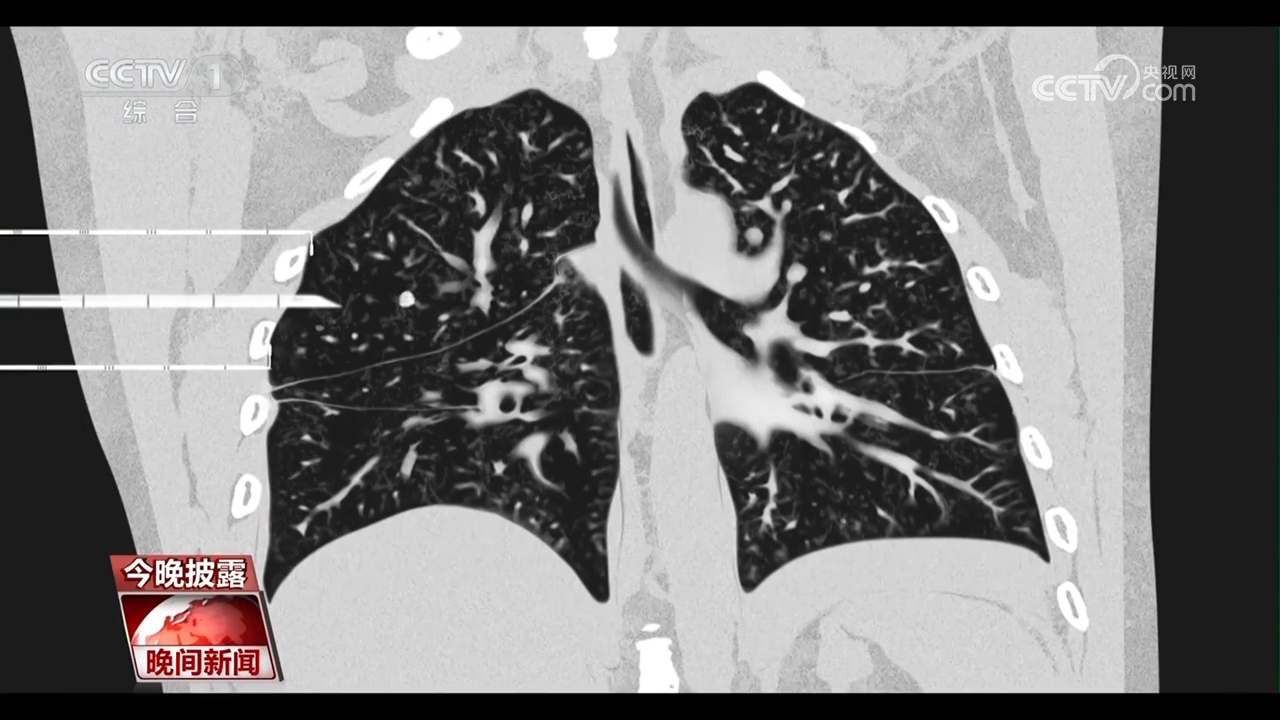

央视网消息:每年的11月是“全球肺癌关注月”。肺癌是我国发病率、死亡率最高的恶性肿瘤。随着胸部CT的普及,越来越多的肺结节被筛查出来。眼下正值年底体检高峰,一旦体检发现肺结节,就意味着会有发展成肺癌的风险吗?肺结节是否需要立刻手术呢?

专家介绍,2毫米以上的结节都能在CT上发现。肺结节不等于肺癌,而且绝大多数是良性的,胸部CT检查初次发现肺结节,先不要恐慌,应根据医生的建议定期复查,观察肺结节的变化。

首都医科大学宣武医院胸外科首席专家 支修益:特别是复合肺结节直径小于等于3厘米的磨玻璃结节,95%以上都是良性的,我们通过观察它的大小、边缘、密度的变化,来决定是否需要临床干预,而小于6毫米的,我们根本就不干预,年度健康体检就可以了。

虽然大部分的肺结节是良性的,不需要治疗,但近些年来,40到50岁左右的肺癌患者明显增多。由于肺癌的早期症状不明显,70%到80%的患者确诊时已是中晚期。因此,专家提醒,50岁以上的高危人群至少应做一次胸部CT进行肺癌的早期筛查。